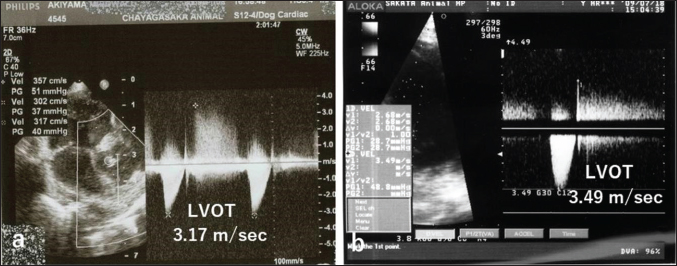

Auscultation revealed a heart rate of 150 beats/minutes and a grade 4/6 systolic murmur in the precordial region near the sternum. Electrocardiography revealed a mean electrical axis of +82º and a mitral P wave in the II, III, and aVF leads. Thoracic radiography showed moderate heart enlargement (vertebral heart score, 10 vertebrae; cardio-thoracic ratio [CTR]: 70%) and increased opacity of the pulmonic field. B-mode echocardiography revealed a small polypoid mass at the dorsal part of the interventricular septum below the aortic valve (Fig. 1a). Two areas of flow acceleration were evident, leading to the mosaic pattern on colour flow Doppler echocardiography: one due to a membranous VSD of 3.17 mm in diameter and the other due to LVOT obstruction caused by the mass (Fig. 1b). In the continuous-wave Doppler (CWD) mode, the LVOT blood flow velocity was 4.55 m/seconds, with a calculated systolic pressure gradient (ΔP) of 83 mmHg between the left ventricle (LV) and aorta (Fig. 2a), and the VSD blood flow velocity was 4.55 m/seconds, with a calculated systolic ΔP of 83 mmHg between the LV and right ventricle (RV) (Fig. 2b). Aortic regurgitation (AR) (Fig. 2a) was also observed. In the CWD mode, the AR blood flow velocity was 3.11 m/seconds, with a calculated diastolic ΔP of 39 of mmHg between the aorta and LV (Fig. 2a).

Fig. 2. CWD echocardiography of the right parasternal long-axis view. (a) The blood flow velocity in the left ventricular outflow tract (LVOT) was 4.55 m/seconds, with a calculated systolic pressure gradient (ΔP) of 83 mmHg between the LV and aorta (AO). The AR blood velocity was 3.11 m/seconds, with a calculated diastolic ΔP of 39 mmHg between the LV and AO. (b) The blood flow velocity in the ventricular septal defect (VSD) was 4.55 m/seconds, with a calculated systolic ΔP of 83 mmHg between the LV and RV. The peak velocity measurement of LVOT, AR, and VSD is not accurate, because of measurements taken using the “beard” instead of the “chin” (see “Study Limitations”).

Fig. 4. CWD echocardiography after surgery. (a) Five days after surgery, the systolic pressure gradient (ΔP) between the LV and aorta (AO) had decreased from 83 mmHg (the preoperative value) to 40 mm Hg. The corresponding values for left ventricular outflow tract (LVOT) velocity were 4.55 and 3.17 m/seconds, respectively. (b) Thereafter, the values were essentially unchanged and were 48.7 mmHg (ΔP) and 3.49 m/seconds (LVOT) at 8.5 months.

The dog was monitored daily with physical examinations, including echocardiography, and the postoperative course was good. However, the dog remained in our hospital for 10 days until discharge to accommodate the owner, who lived remotely. Postoperative auscultation revealed a persistent grade 2/6 systolic murmur, and colour Doppler echocardiography revealed slight residual shunt blood flow through the VSD. As shown via thoracic radiography, the CTR was lower after surgery (66% at 10 days and 65.9% at 8.5 months) than before surgery (70%). As shown via CWD echocardiography, the systolic ΔP between the LV and aorta was also lower after surgery (40 mmHg at 5 days) than before surgery (83 mmHg) (Fig. 4a); after 5 days, it remained essentially unchanged and was 48.7 mmHg at 8.5 months (Fig. 4b). At 8.5 months, the dog had no clinical signs of heart disease and her body weight had increased to 3.9 kg. According to the referral hospital, the dog had no cardiac complications during the next 11 years.

Echocardiography is the best tool for the detection of intracardiac tumour, especially obstructive myxomas (Bright et al., 1990; Ori et al., 1994; Fernandez-del Palacio et al., 2011; Šimundić et al., 2019; Stack et al., 2021; Mellish et al., 2022). In the present case, auscultation, electrocardiography, and thoracic radiography were also useful. B-mode, colour (Fig. 1a, b), and CWD (Fig. 2a, b) echocardiography clearly revealed a small polyploid mass that moderately obstructed the LVOT, as well as AR and a membranous VSD. The VSD likely caused the AR.

In our study, CWD echocardiography was especially useful for monitoring blood flow velocity by calculating ΔP before and after surgery. As determined using this modality, the systolic ΔP between the LV and aorta was 83 mmHg immediately before surgery. According to the referral hospital, it was 50.7 mmHg 2 months before surgery. This slow increase in the ΔP presumably reflected the slow growth of the tumour, which was likely benign (Han et al., 2012). Five days after surgery, the ΔP had decreased to 40 mmHg (Fig. 4a), with little change over the next 8.5 months (Fig. 4b). Although echocardiography may indicate whether a tumour is benign or malignant, biopsy is required for definitive diagnosis of a cardiac myxoma.

For CWD echocardiography, Kyranis et al. (2018) identified the measurement site for peak velocities on Doppler wave to ensure the exact value is taken at the “chin” and not the “beard”. In this case (Fig. 2a and b), we measured the peak velocities at the beard, not the chin. Therefore, the exact volume appears to be slightly lower. However, this cannot be corrected because of a lack of original image data. On echocardiographic assessment of the LVOT, pulsed-wave Doppler (PWD) is used for LVOT flow evaluation when no flow acceleration is noted to accurately measure the specific velocity at the region of interest. When there is a fixed obstruction or dynamic obstruction (as is possible in this case owing to the mobile mass) leading to flow acceleration, then aliasing of PWD can occur, which forces us to use CWD for evaluation of the peak velocity and peak gradient (Koplitz et al., 2006). However, in our case, we did not obtain PWD data.